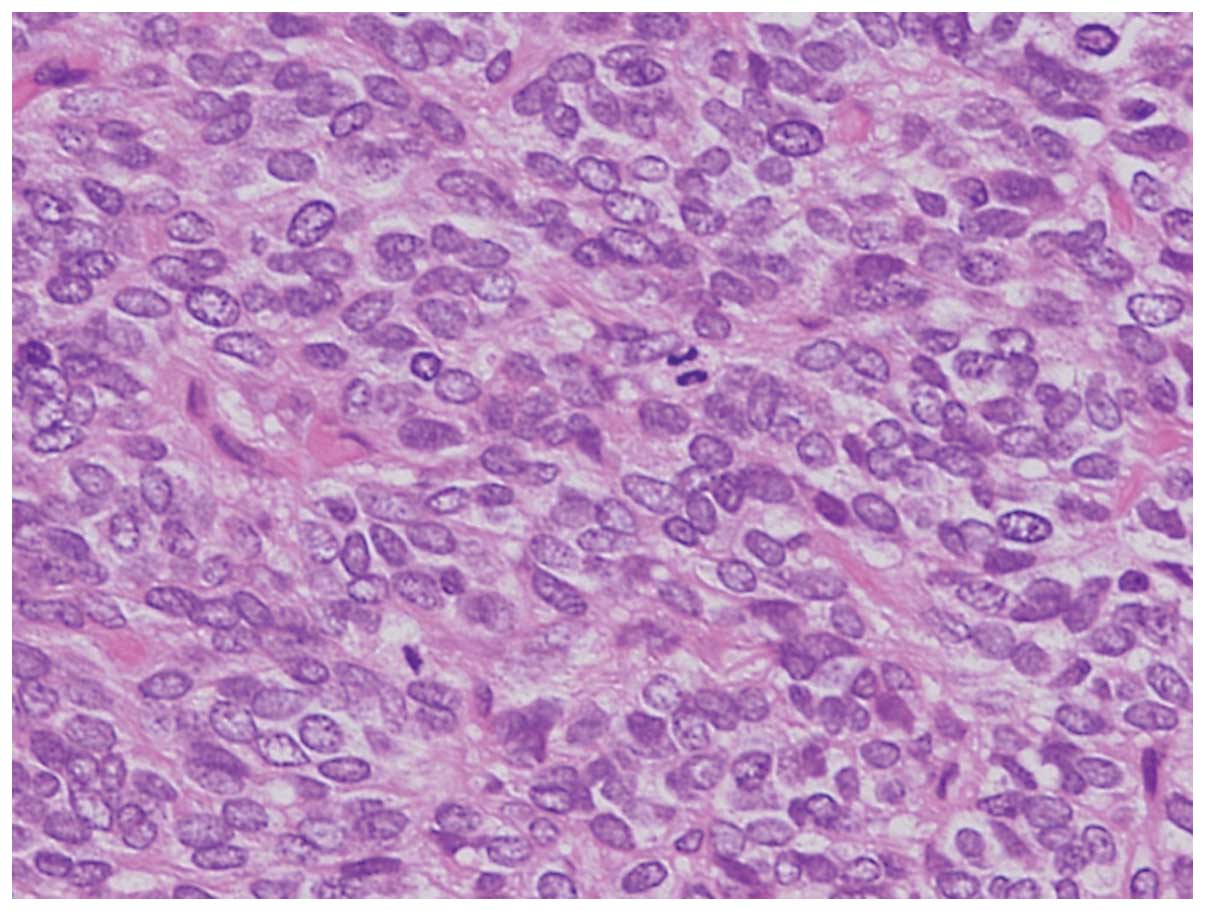

Микрофотографии гистологии глиобластомы головного мозга